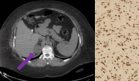

Los análisis iniciales evidenciaron una anemia microcítica hipocrómica significativa (hemoglobina 7,4 mg/dL, hematocrito 26%, VCM 67 mg/dL, HCM 19,5 mg/dL), sin alteraciones en los marcadores tumorales. Una tomografía computarizada de abdomen y pelvis mostró una masa irregular de 65×35×31 mm con densidad de tejido blando que comprometía el ciego y el colon ascendente proximal, además de múltiples ganglios linfáticos regionales aumentados de tamaño. La colonoscopia reveló una lesión cecal circunferencial, ulcero-proliferativa, de aspecto maligno. No se observaron metástasis a distancia en la tomografía de estadificación.

El estudio histopatológico confirmó la presencia de un carcinoma invasivo con patrón de crecimiento sincitial, denso infiltrado linfocítico del huésped y necrosis sucia, hallazgos característicos del carcinoma medular (CM) de colon. El tumor comprometía la grasa subserosa (pT4a) y se detectaron metástasis en 13 de 22 ganglios linfáticos (pN2b), con invasión linfovascular prominente. Los márgenes quirúrgicos se encontraban libres de tumor (resección R0).